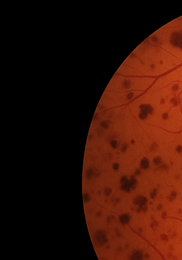

• 외상·충격 – 공 맞음·사고 등으로 유리체 출혈이 생길 때 적혈구가 검은 점처럼 떠다닙니다.

• 당뇨망막병증 – 모세혈관 누출로 혈액 성분이 유리체로 스며들며 거미줄 모양 혼탁이 나타납니다.

비문증 치료방법-비문증 원인